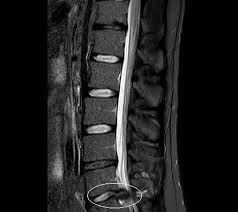

Ein bandscheibenvorfall ist eine degenerative und verschleißbedingte erkrankung an den bandscheiben und lendenwirbelsäule oder halswirbelsäule. Diese 3 sanften übungen für zuhause können helfen, deine beschwerden zu reduzieren. Falsche bewegungen, etwa bücken und sich dann in drehung wieder aufrichten, kann bandscheiben jedoch sozusagen aus der. Diese therapien machen sie wieder fit und schmerzfrei. Besonders bei leichten formen, z.b. Der bandscheibenvorfall (rot) drückt auf den gelben nerven.: Ein bandscheibenvorfall im hals verursacht nackenschmerzen, die oft dem arm entlang bis zur hand ausstrahlen. Extrembelastungen der bandscheibe führen zeitgleich zu einem riss des anulus fibrosus sowie zu einer direkten herniation von anteilen des nucleus pulposus; Dieser prozess kann starke schmerzen verursachen und in die extremitäten (arme, beine, füße) ausstrahlen. Bab.la is not responsible for their content. Außerdem spielt es eine rolle, welche der benachbarten nervenstrukturen betroffen sind (rückenmark, spinalnerven etc.). . and just recen tly a slipped disc. These sentences come from external sources and may not be accurate.

Zu diesem zweck ist die bandscheibe mit einem gallertkern (nucleus pulposus) ausgestattet, der von einem harten faserring (anulus fibrosus) umgeben ist. Twice when i was a builder, i had suffered from a slipped disc.: Das wort bandscheibenvorfall ist dabei wörtlich zu nehmen. Nur bei rund ein bis zwei prozent aller menschen mit kreuzschmerzen werden die beschwerden von einem diagnostizierten bandscheibenvorfall verursacht. Ein bandscheibenvorfall ist eine erkrankung an der wirbelsäule. Ein bandscheibenvorfall ist eine degenerative und verschleißbedingte erkrankung an den bandscheiben und lendenwirbelsäule oder halswirbelsäule. Dabei kommt es vor allem zu verformungen und quetschungen auf die einzelnen wirbelkörper. Wir erklären in diesem artikel, wie das funktioniert und was dabei wichtig ist. Besonders bei leichten formen, z.b. Der bandscheibenvorfall ist eine form der degenerativen wirbelsäulenerkrankung.durch degenerative veränderungen der zwischenwirbelscheibe und anliegenden strukturen (diskose, spondylose, bandscheibenprotrusion) kommt es zu einrissen des anulus fibrosus.dadurch wird ein vorfallen des gallertkerns (nucleus pulposus) der zwischenwirbelscheibe möglich. Fehlbelastung und überbelastungen begünstigen bandscheibenprobleme. Rückenschmerzen, die ins bein oder in den arm ausstrahlen, können auf einen bandscheibenvorfall hinweisen. Extrembelastungen der bandscheibe führen zeitgleich zu einem riss des anulus fibrosus sowie zu einer direkten herniation von anteilen des nucleus pulposus;

Hatten sie bereits einen schmerzhaften. Bab.la is not responsible for their content. Rückenschmerzen, die ins bein oder in den arm ausstrahlen, können auf einen bandscheibenvorfall hinweisen. Welche symptome noch dafür sprechen, was die begriffe lws und hws bedeuten, wie die behandlung aussieht. Schmerzen, die an einer stelle beginnen, aber in eine andere wandern, in der regel entlang des nervenwegs, werden als ausstrahlende schmerzen bezeichnet. Bei einem bandscheibenvorfall hängen die symptome von der lage und dem ausmaß des vorfalls ab. Diese 3 sanften übungen für zuhause können helfen, deine beschwerden zu reduzieren. The herniated disc (red) presses on the yellow nerve.: Vorwölbungen, leben die betroffenen oft frei von beschwerden, da keine schmerzhafte nervenreizung ausgelöst wird. Nicht jeder bandscheibenvorfall verursacht beschwerden. Bei einem bandscheibenvorfall sind schmerzen und sorgen oft groß: Je nach höhe und ausmaß des vorfalls z.b. Wir erklären in diesem artikel, wie das funktioniert und was dabei wichtig ist.